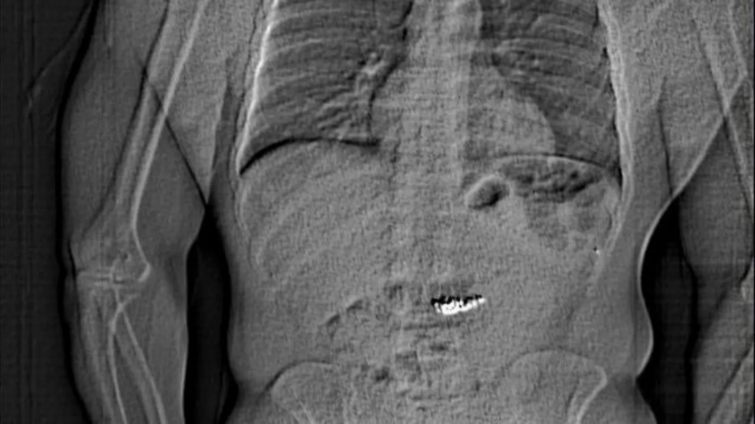

Police later released an x-ray that appeared to show an individual's abdomen with a foreign object inside.